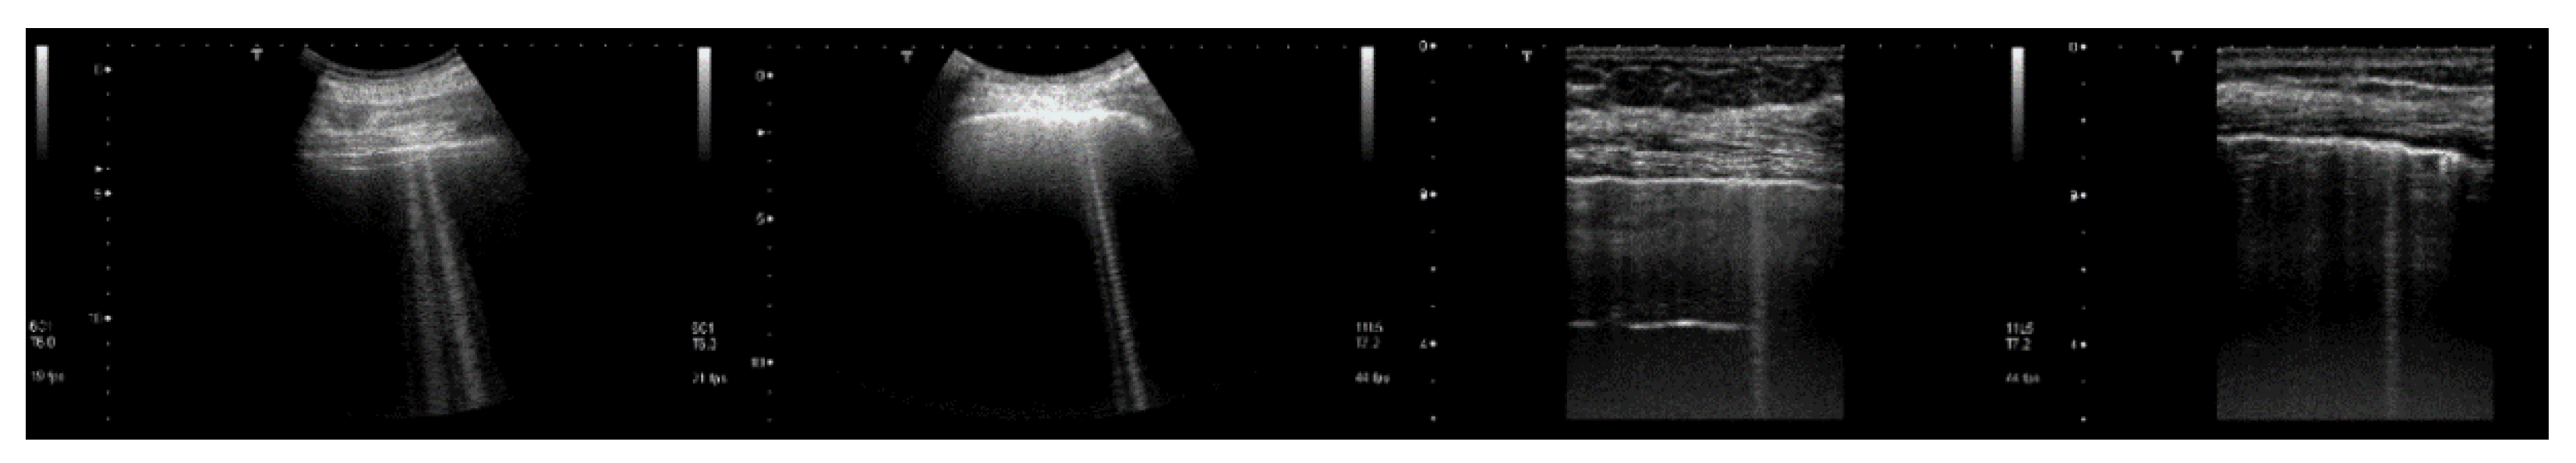

Figure 8, from left to right, shows the details of the artifacts which were obtained on agar cusps with a thickness t equal to 2, 1, 0.5, 0.3, and 0.1 mm, respectively (see Figure 3). A distance of about 4 mm, between the upper polyethylene film and the first reflection generated by the agar cusps, is derived from the figure, according to the assumed propagation speed of 1500 m/s. This means that the US pulse, once it has been transmitted to the ridge of the agar cusps, propagates through the agar sample and reaches the lower polyethylene film before being reflected towards the probe. Figure 8 shows how modulated B-lines are obtained when the thickness t of the coupling section is equal to 0.5, 0.3, and 0.1 mm, and how confused artifacts are obtained when the latter increases. A slightly confused modulation was obtained when the thickness of the cusp ridge was equal to 1 mm. Modulated artifacts, such as those observed in cardiogenic pathologies, are finally obtained for the first time on deterministic phantoms, and they seem to be correlated to the size of the acoustic channel which links the acoustic trap to the chest wall.

Figure 9 shows four lung US images which have been selected from a data set previously acquired by means of a Toshiba Aplio XV scanner in our Respiratory Department during a study which was approved by the local Ethics Committee CEAVNO (study number 1089 approved on January 30, 2017). The two images on the left were acquired with a PVT-375BT convex probe and a central frequency equal to 6 MHz. The two images on the right were acquired with a PLT-704AT linear probe and a central frequency of 7.2 MHz. From left to right, the first image shows two B-lines; the first B-line does not show any modulation, while the second shows a slightly confused modulation. The second image shows a modulated B-line and the third shows a non-modulated B-line. The last image on the right shows a modulated B-line. An analogy with the experimental results illustrated in Figure 8 emerges, and the physicians’ hypothesis regarding the progression of a lung disorder supports this thesis. According to their hypothesis, the interstitial spaces between the alveoli gradually increase with the progression of a pathology, and the modulated B-lines are related only to the early stages of the pathology.

Figure 8. From left to right, the figure shows the vertical artifacts which were obtained with models of agar cusps having a thickness t of the upper part equal to 2, 1, 0.5, 0.3, and 0.1 mm, respectively. The two thick white lines at the top and at the bottom of the images represent the reflection of the upper polyethylene film and its replica, respectively.

Figure 9. From left to right, the first image shows two B-lines; the first B-line does not show any modulation, while the second shows a slightly confused modulation. The second image shows a modulated B-line, and the third shows a non-modulated B-line. The last image on the right shows a modulated B-line.